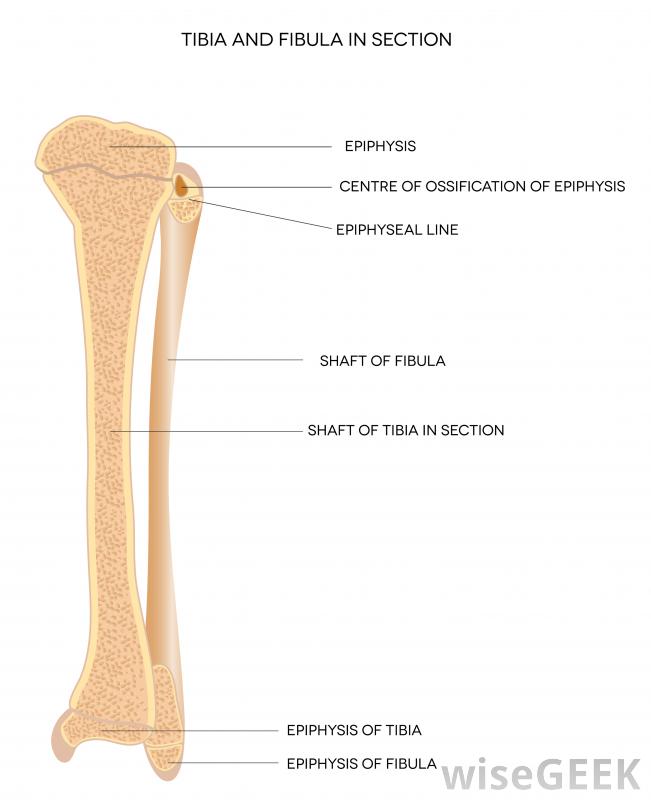

腓骨是小腿较细的长骨。

膝盖示意图,显示腓骨。